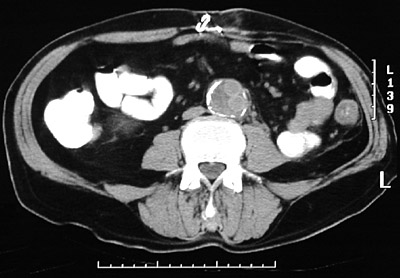

| This abdominal CT scan was taken postoperatively in a patient who underwent an aorto-iliac graft because of severe aortic atherosclerosis with signficant iliac arterial occlusion. This view is just above the aortic bifurcation, and the graft material can be seen in the residual lumen of the native aorta, the wall of which is highlighted by bright calcification of atheromatous plaque. |